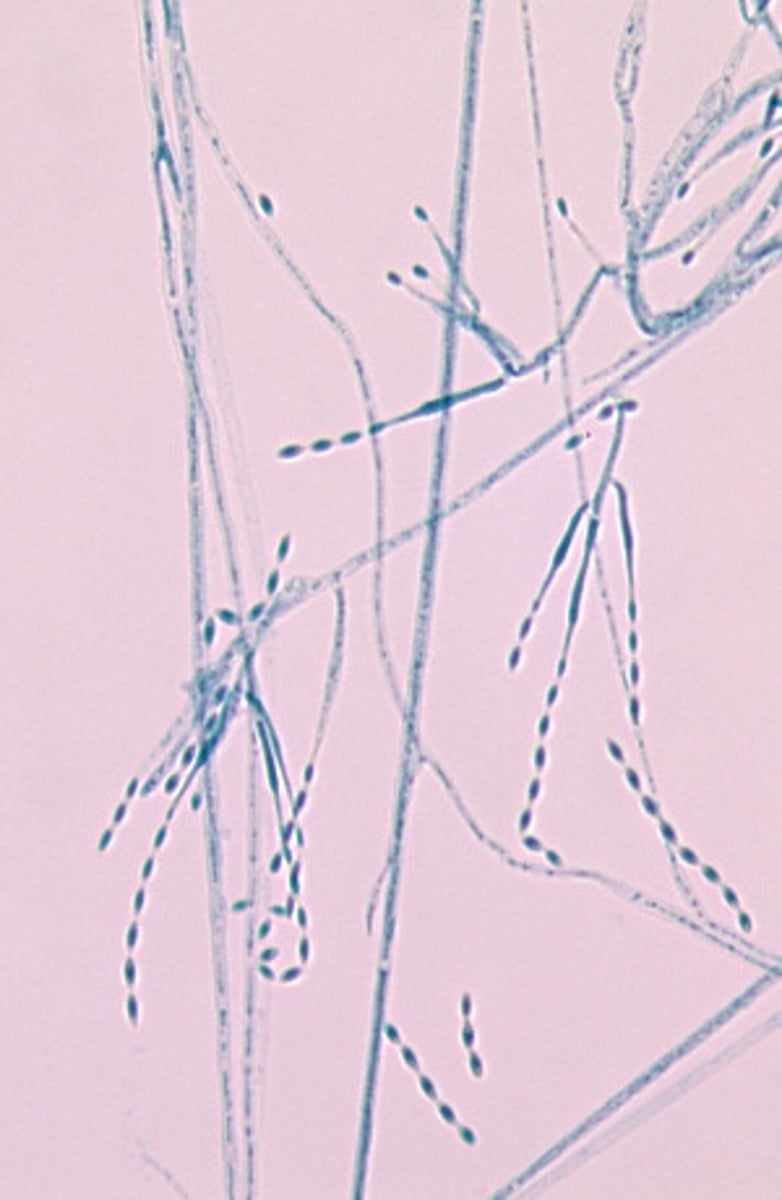

This microscopic image suggests which of the following fungi?

Paecilomyces spp. produce widely-spaced, elongated, slender phialides bearing chains of oval conidia.